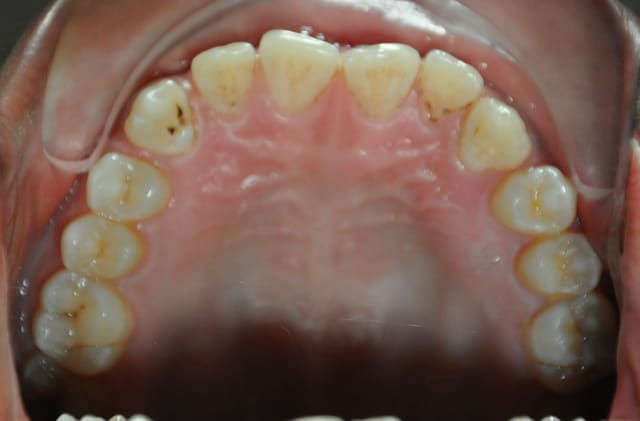

cas clinique:articulé débordant d'un seul coté

comment on peut traiter cet articulé gauche

Concernant l’occlusion croisée à gauche, il y a deux problèmes : un problème vertical d’égression à partir des canines et un problème transversal.

Corrige d'abord le problème vertical, l’occlusion croisée sera ensuite relativement facile à traiter avec de simples élastiques.

les dernieres photos du cas